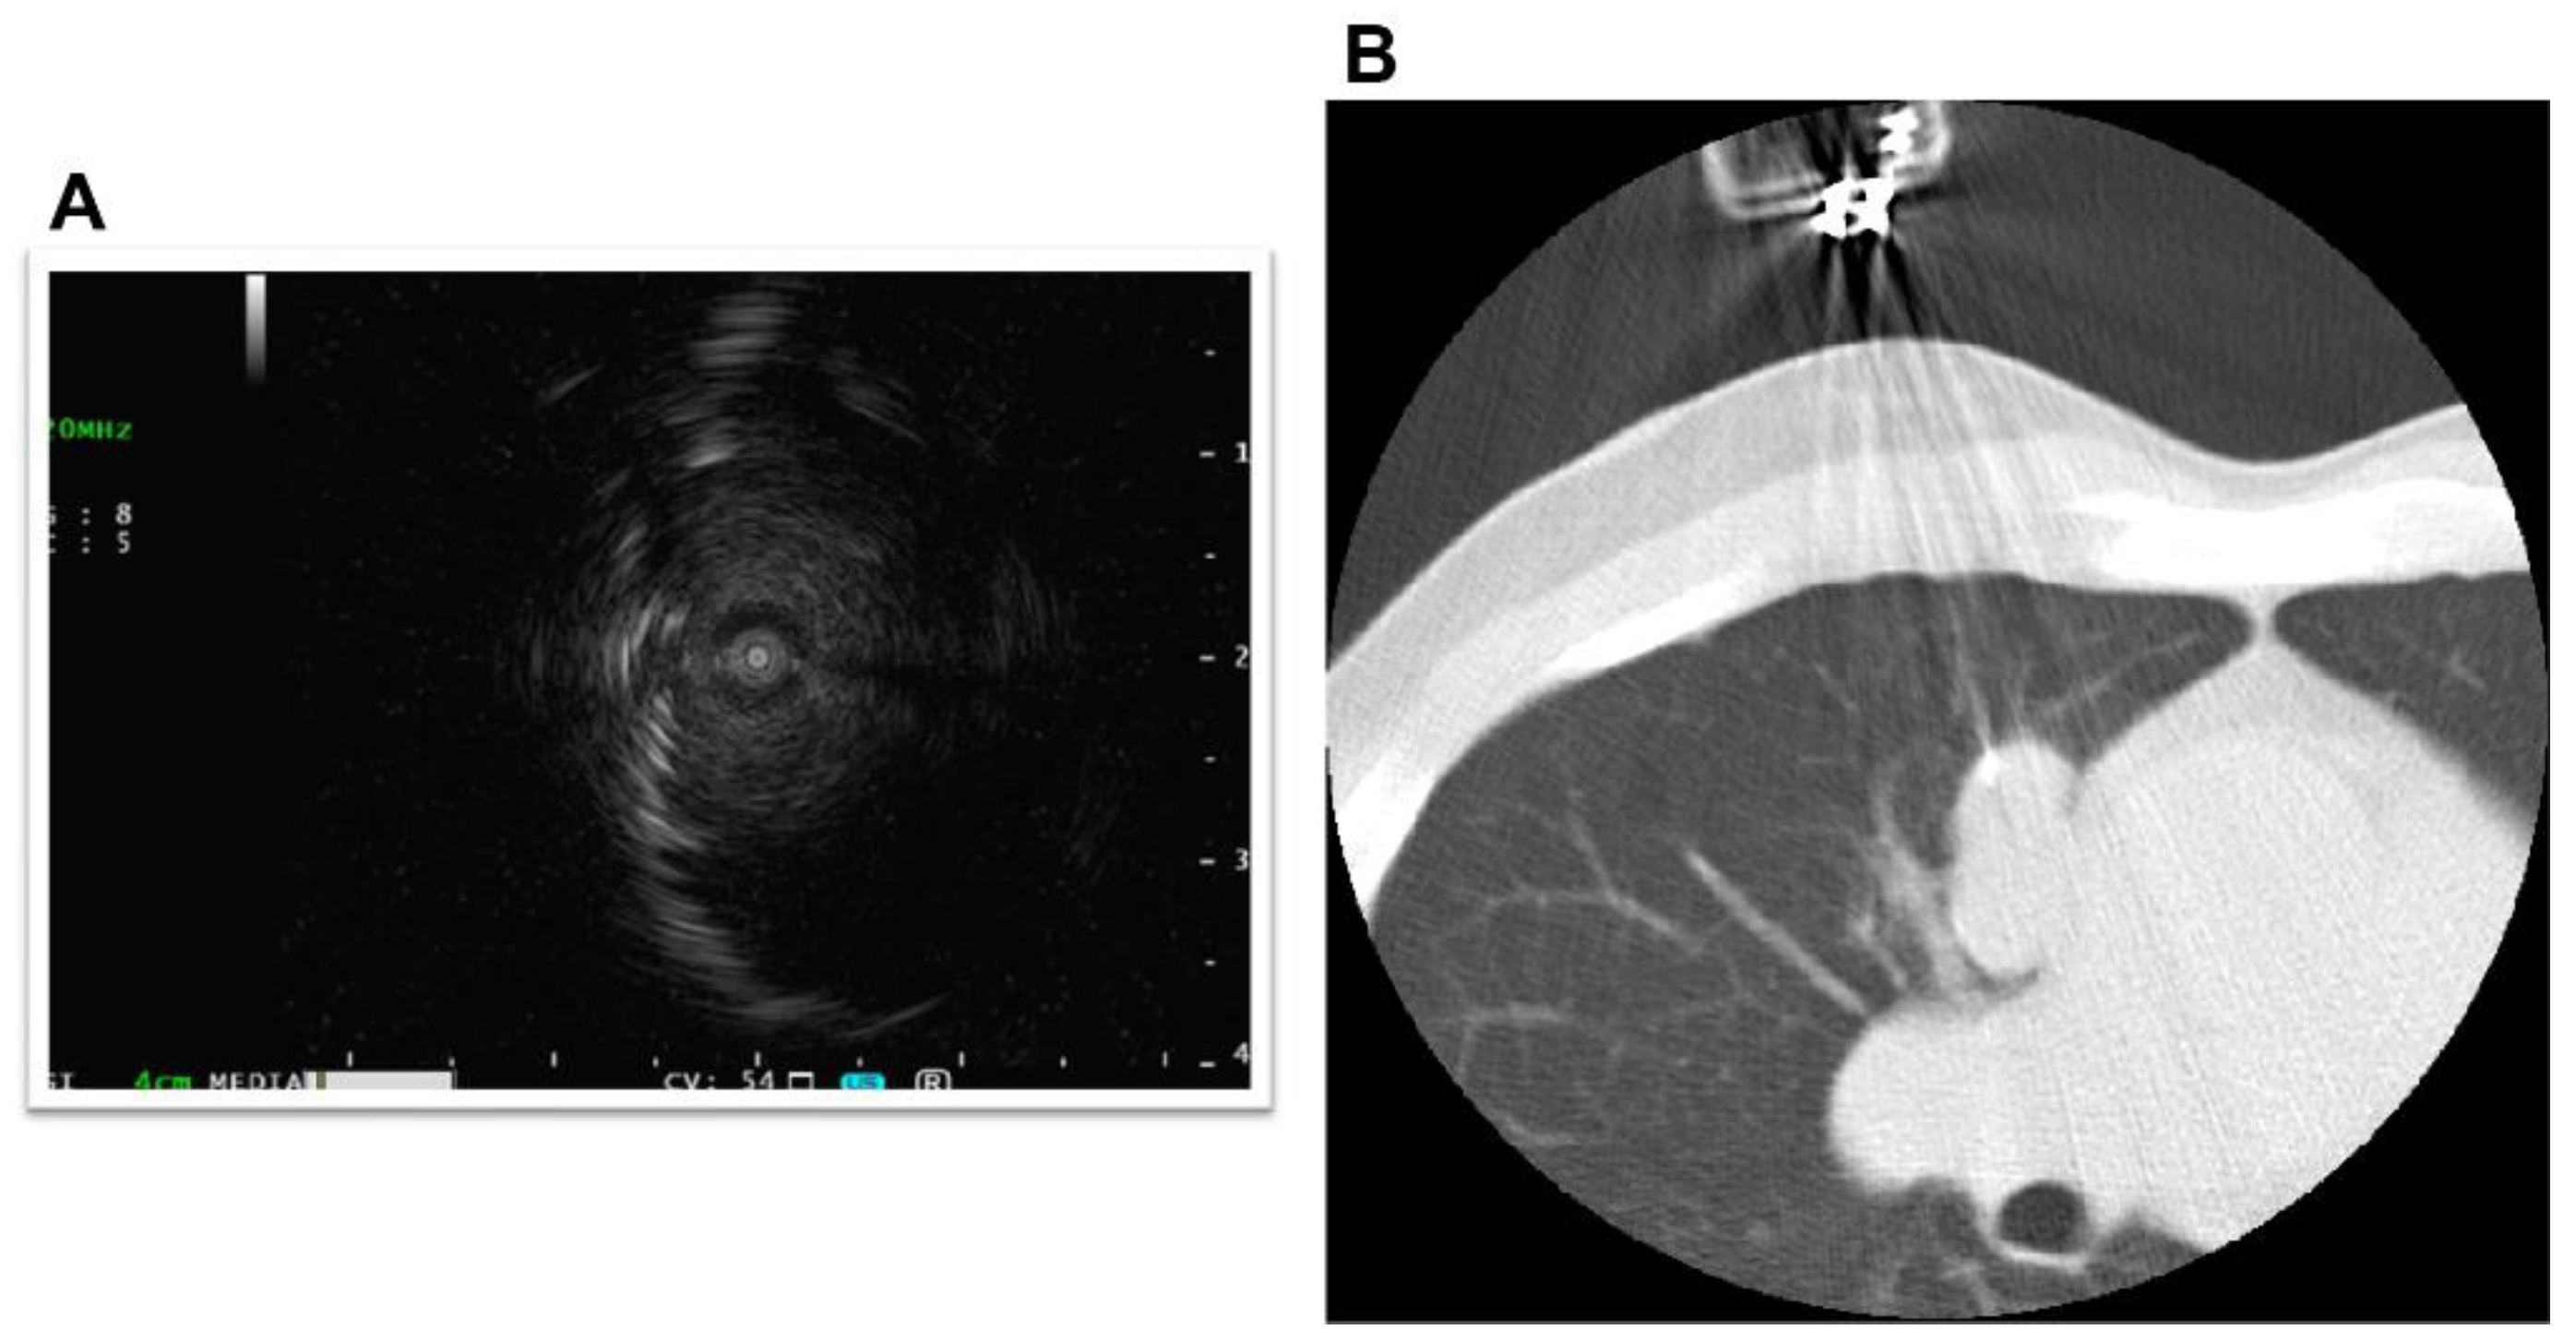

2. Case Presentation